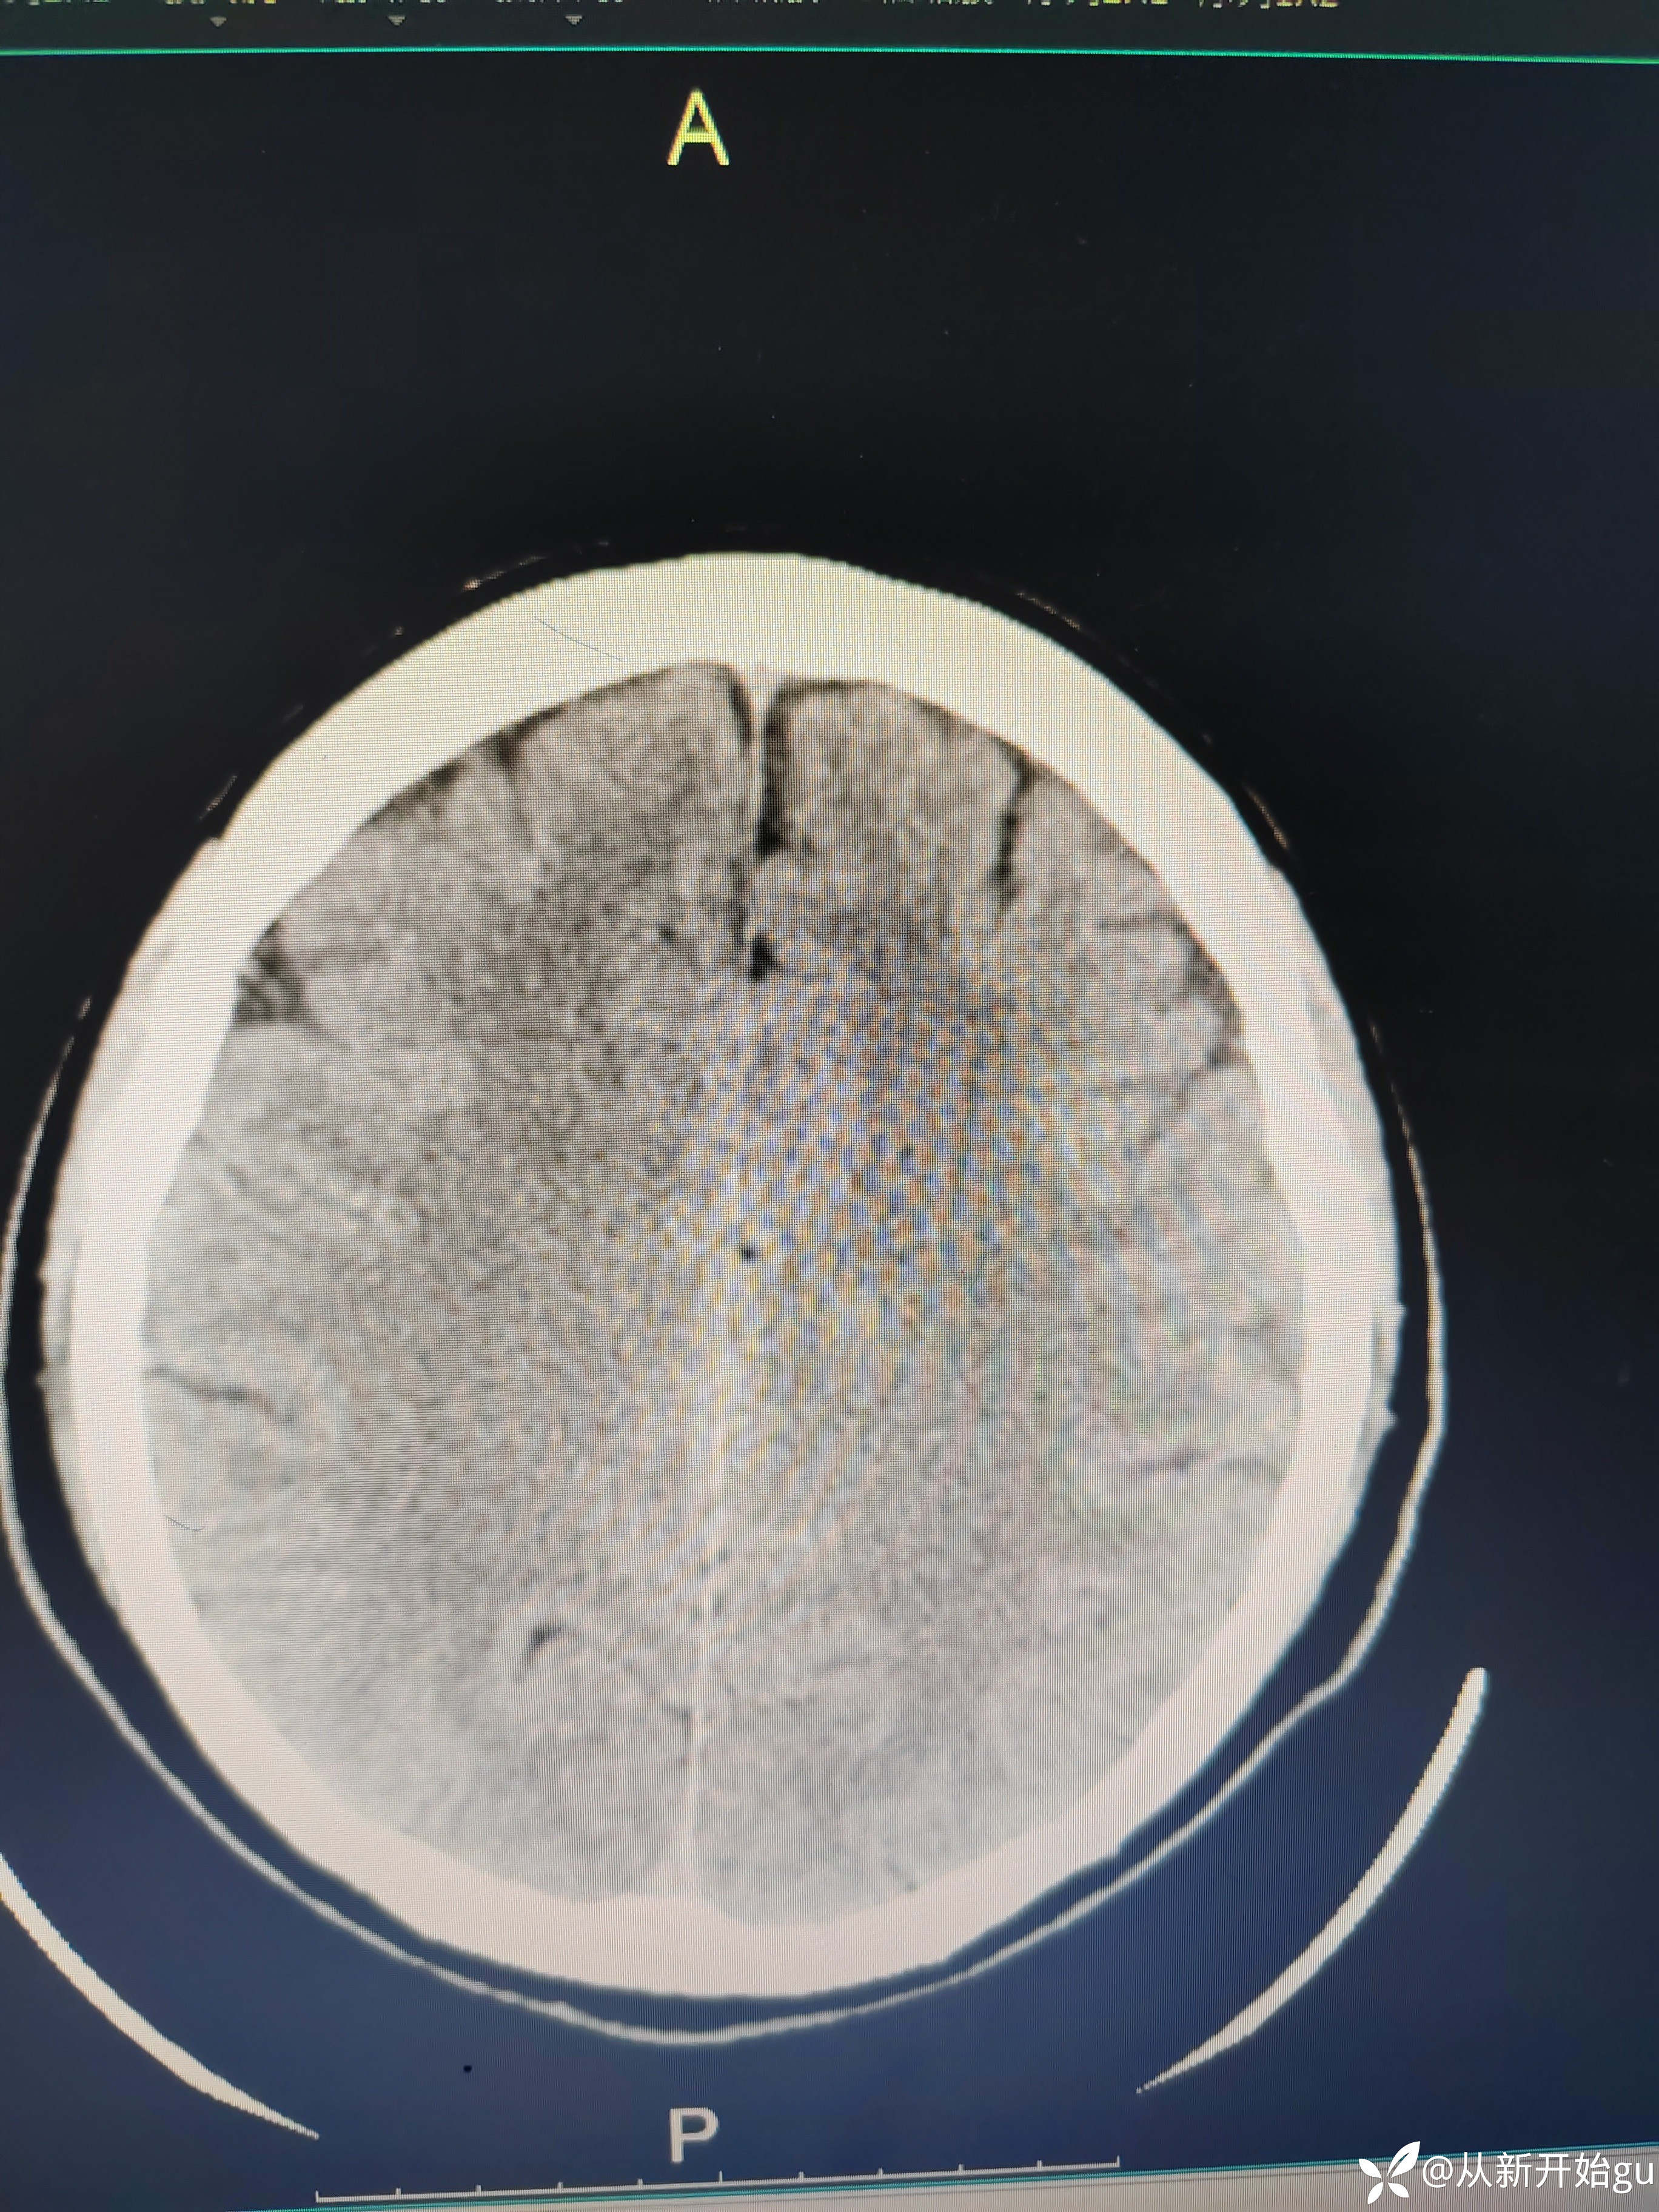

患者51岁男性,主因左下肢活动障碍1小时来院。既往高血压病史,查体,右侧鼻唇沟稍浅(家属诉之前就这样),神舌居中,左侧下肢肌力5级-,左侧跟膝胫试验欠稳准,左侧巴氏征阳性,评分也就一分,鼻唇沟稍浅未纳入。行颅脑CT检查如图所示